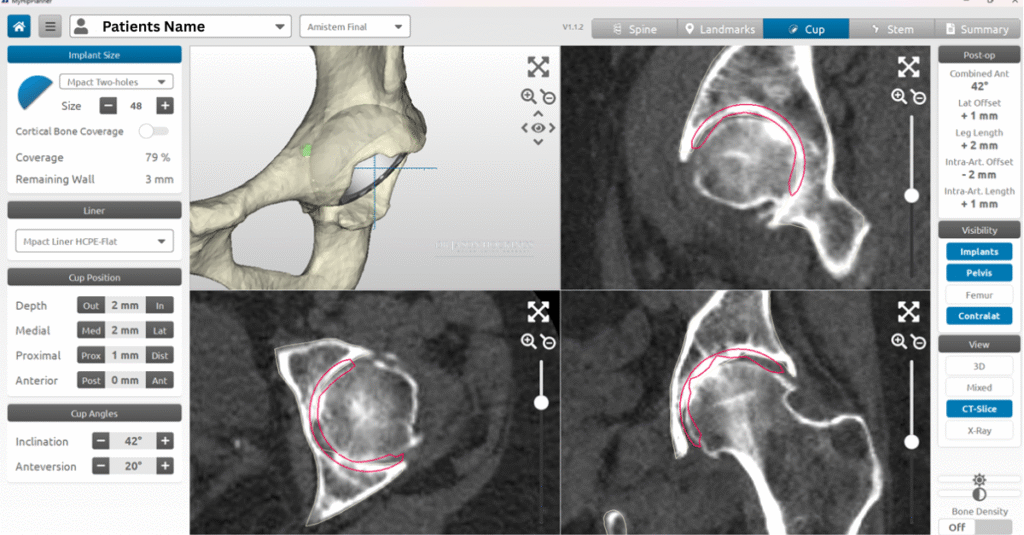

Recognising that every hip is different, Dr Hockings incorporates digital imaging and surgical planning tools to measure your anatomy before surgery, plan component sizes, and optimise placement of the implants. This means that, for suitable patients, patient-specific instrumentation (PSI) may be used to tailor the procedure to your exact bone shape and alignment.

If total hip replacement is considered the most appropriate treatment, Dr Hockings will organise further diagnostic imaging to assist with surgical planning. You’ll be referred for a CT scan, which is used to create a 3D model of your hip using MyHip software for precise, patient-specific planning. Additional tests such as X-rays, blood tests, and general health checks may also be arranged as needed.

Once your CT scan has been completed, Dr Jason Hockings will use the data to develop a personalised 3D surgical plan using MyHip digital planning software. This system allows him to visualise your hip joint in three dimensions and assess your bone shape, joint orientation, and surrounding anatomy with precision.

Using this model, Dr Hockings can plan the size, position, and alignment of each implant component before surgery. This planning helps guide leg length, joint stability, and muscle balance while minimising the need for adjustments during the procedure.

Preparing the hip socket: The acetabulum is reshaped and smoothed to create a stable foundation for the new socket component. The MyHip plan helps guide the position, angle, and depth of preparation so the implant sits securely and functions smoothly.

Preparing the femur: The femur is prepared to receive the stem component. Specialised instruments shape the canal inside the thigh bone in line with the 3D plan. A trial stem and trial head are then placed to check leg length, implant angles, soft tissue tension, and overall joint stability.